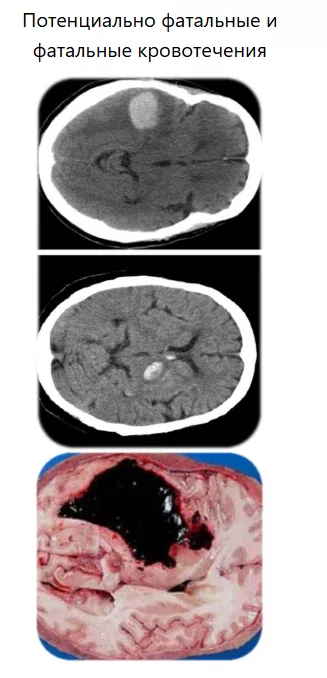

Потенциально фатальные и фатальные кровотечения

Риск кровотечений возрастает с уровня тромбоцитов менее 50 тыс/мкл8